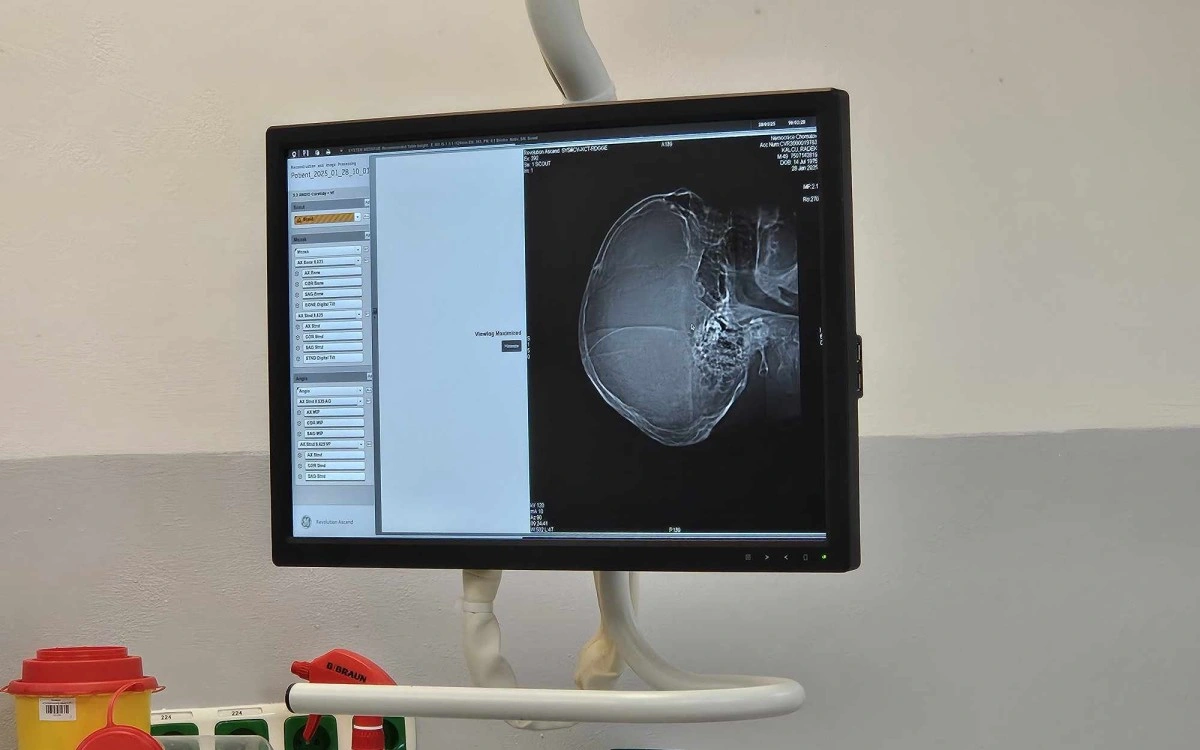

Chomutov – Dva týdny mají zdravotníci v Nemocnici Chomutov k dispozici nový přístroj pro počítačovou tomografii (CT). Samotný přístroj stál přes čtrnáct milionů korun a je z nejnovější generace. Pro pacienty představuje zkrácení vyšetření o polovinu času.

Nový přístroj si za tu krátkou dobu vyzkoušely již desítky pacientů, denně totiž na tomografu vyšetří zdravotníci cca 50 lidí. „Ročně to jsou desítky tisíc lidí. Využíváme jej nejen pro onkologické pacienty či iktové centrum, ale i pro screening plic, hlavy a mozku, při nutnosti odhalení příčin bolesti břicha. De facto jej využíváme pro zobrazení celého těla," dodal primář radiodiagnostického oddělení MUDr. Vijay Chandra Sekar.

Nad lehátkem snímá pacienta kamera, aby jej mohli lékaři neustále kontrolovat. Jak vše funguje, vysvětluje vedoucí radiologický asistent Bc. Alexandr Kuchař. Foto: jip